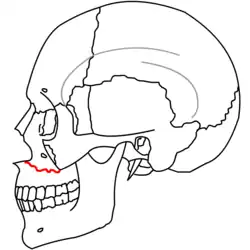

| Fraturas 2 de Le Fort | |

No início do século XX, René Le Fort mapeou as regiões faciais típicas dos traumas maxilo faciais, agora conhecidos como Fraturas I, II, e III de Le Fort (direita).[11] A Fratura I de Le Fort, também chamada de Fratura de Guérin ou Fratura transversa,[12] envolve a maxila, separando-a do palatino.[13] A Fratura II de Le Fort, conhecida também como Fratura piramidal,[12] atravessa os ossos nasais e o aro orbital.[13] A Fratura III de Le Fort, por sua vez, chamada também de Disjunção crâniofacial,[12] atravessa a frente da maxila e envolve as suturas zigomaticofrontal, maxilofrontal nasofrontal, os assoalhos das órbitas, a etmóide e o esfenóide.[12] As Fraturas de Le Fort, responsáveis por 10-20% das fraturas faciais, são frequentemente associadas com outros ferimentos graves.[13] Le Fort fez seu trabalho com base em cadáveres e caveiras, e o sistema de classificação tem sido criticado como impreciso e simplista uma vez que a maioria das fraturas de meia-face envolvem uma combinação das fraturas de Le Fort.[13] Embora a maioria das fraturas faciais não seguem os padrões descritos por Le Fort, seu sistema ainda é utilizado para categorizar os diversos tipos de traumatismos.[14] http://www.angelfire.com/nm/cirurgia/pritra/Image90.gif